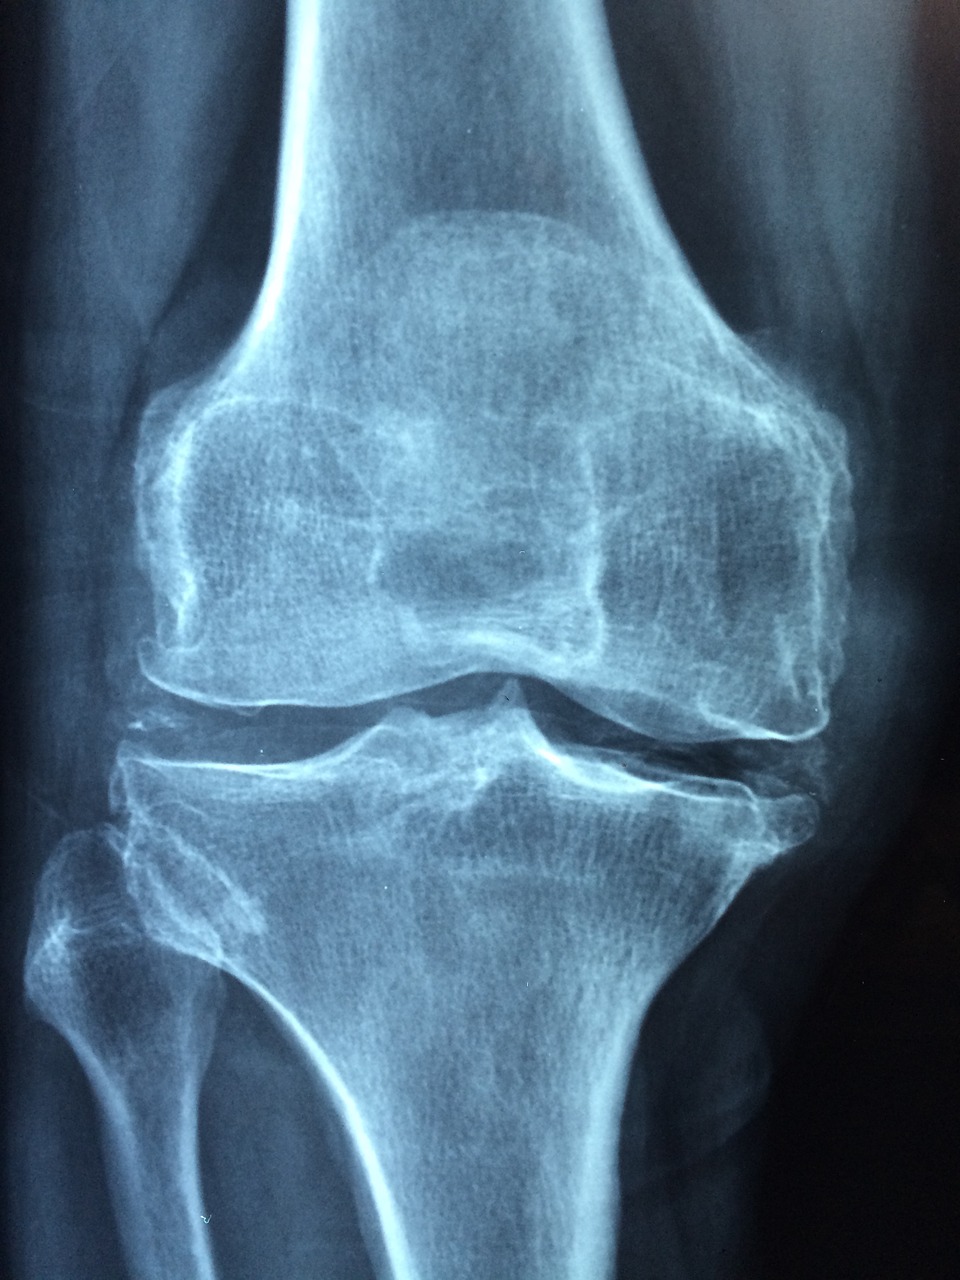

若い頃に重い物を抱えたり持ち運びをしていたら、首や腰や膝の関節痛が出てくる方が多いです。

特に、可動域が大きい部位に負担が掛かっています。

我々の肉体では、神経細胞や筋肉細胞は永久に鍛錬することが可能とはされていますが、関節付近に存在する筋や腱などは、大きな負荷を掛け続けると消耗してしまいます。

足・腰・膝を長持ちさせる為には、無理した時には休養や栄養を十分に摂取することと、必要に応じて鍼灸院や整骨院やカイロプラクティックなどを随時利用して、足・腰・膝に溜まっている毒素を排出して、将来の負債を帳消しにするたゆまぬ努力は必要になります。